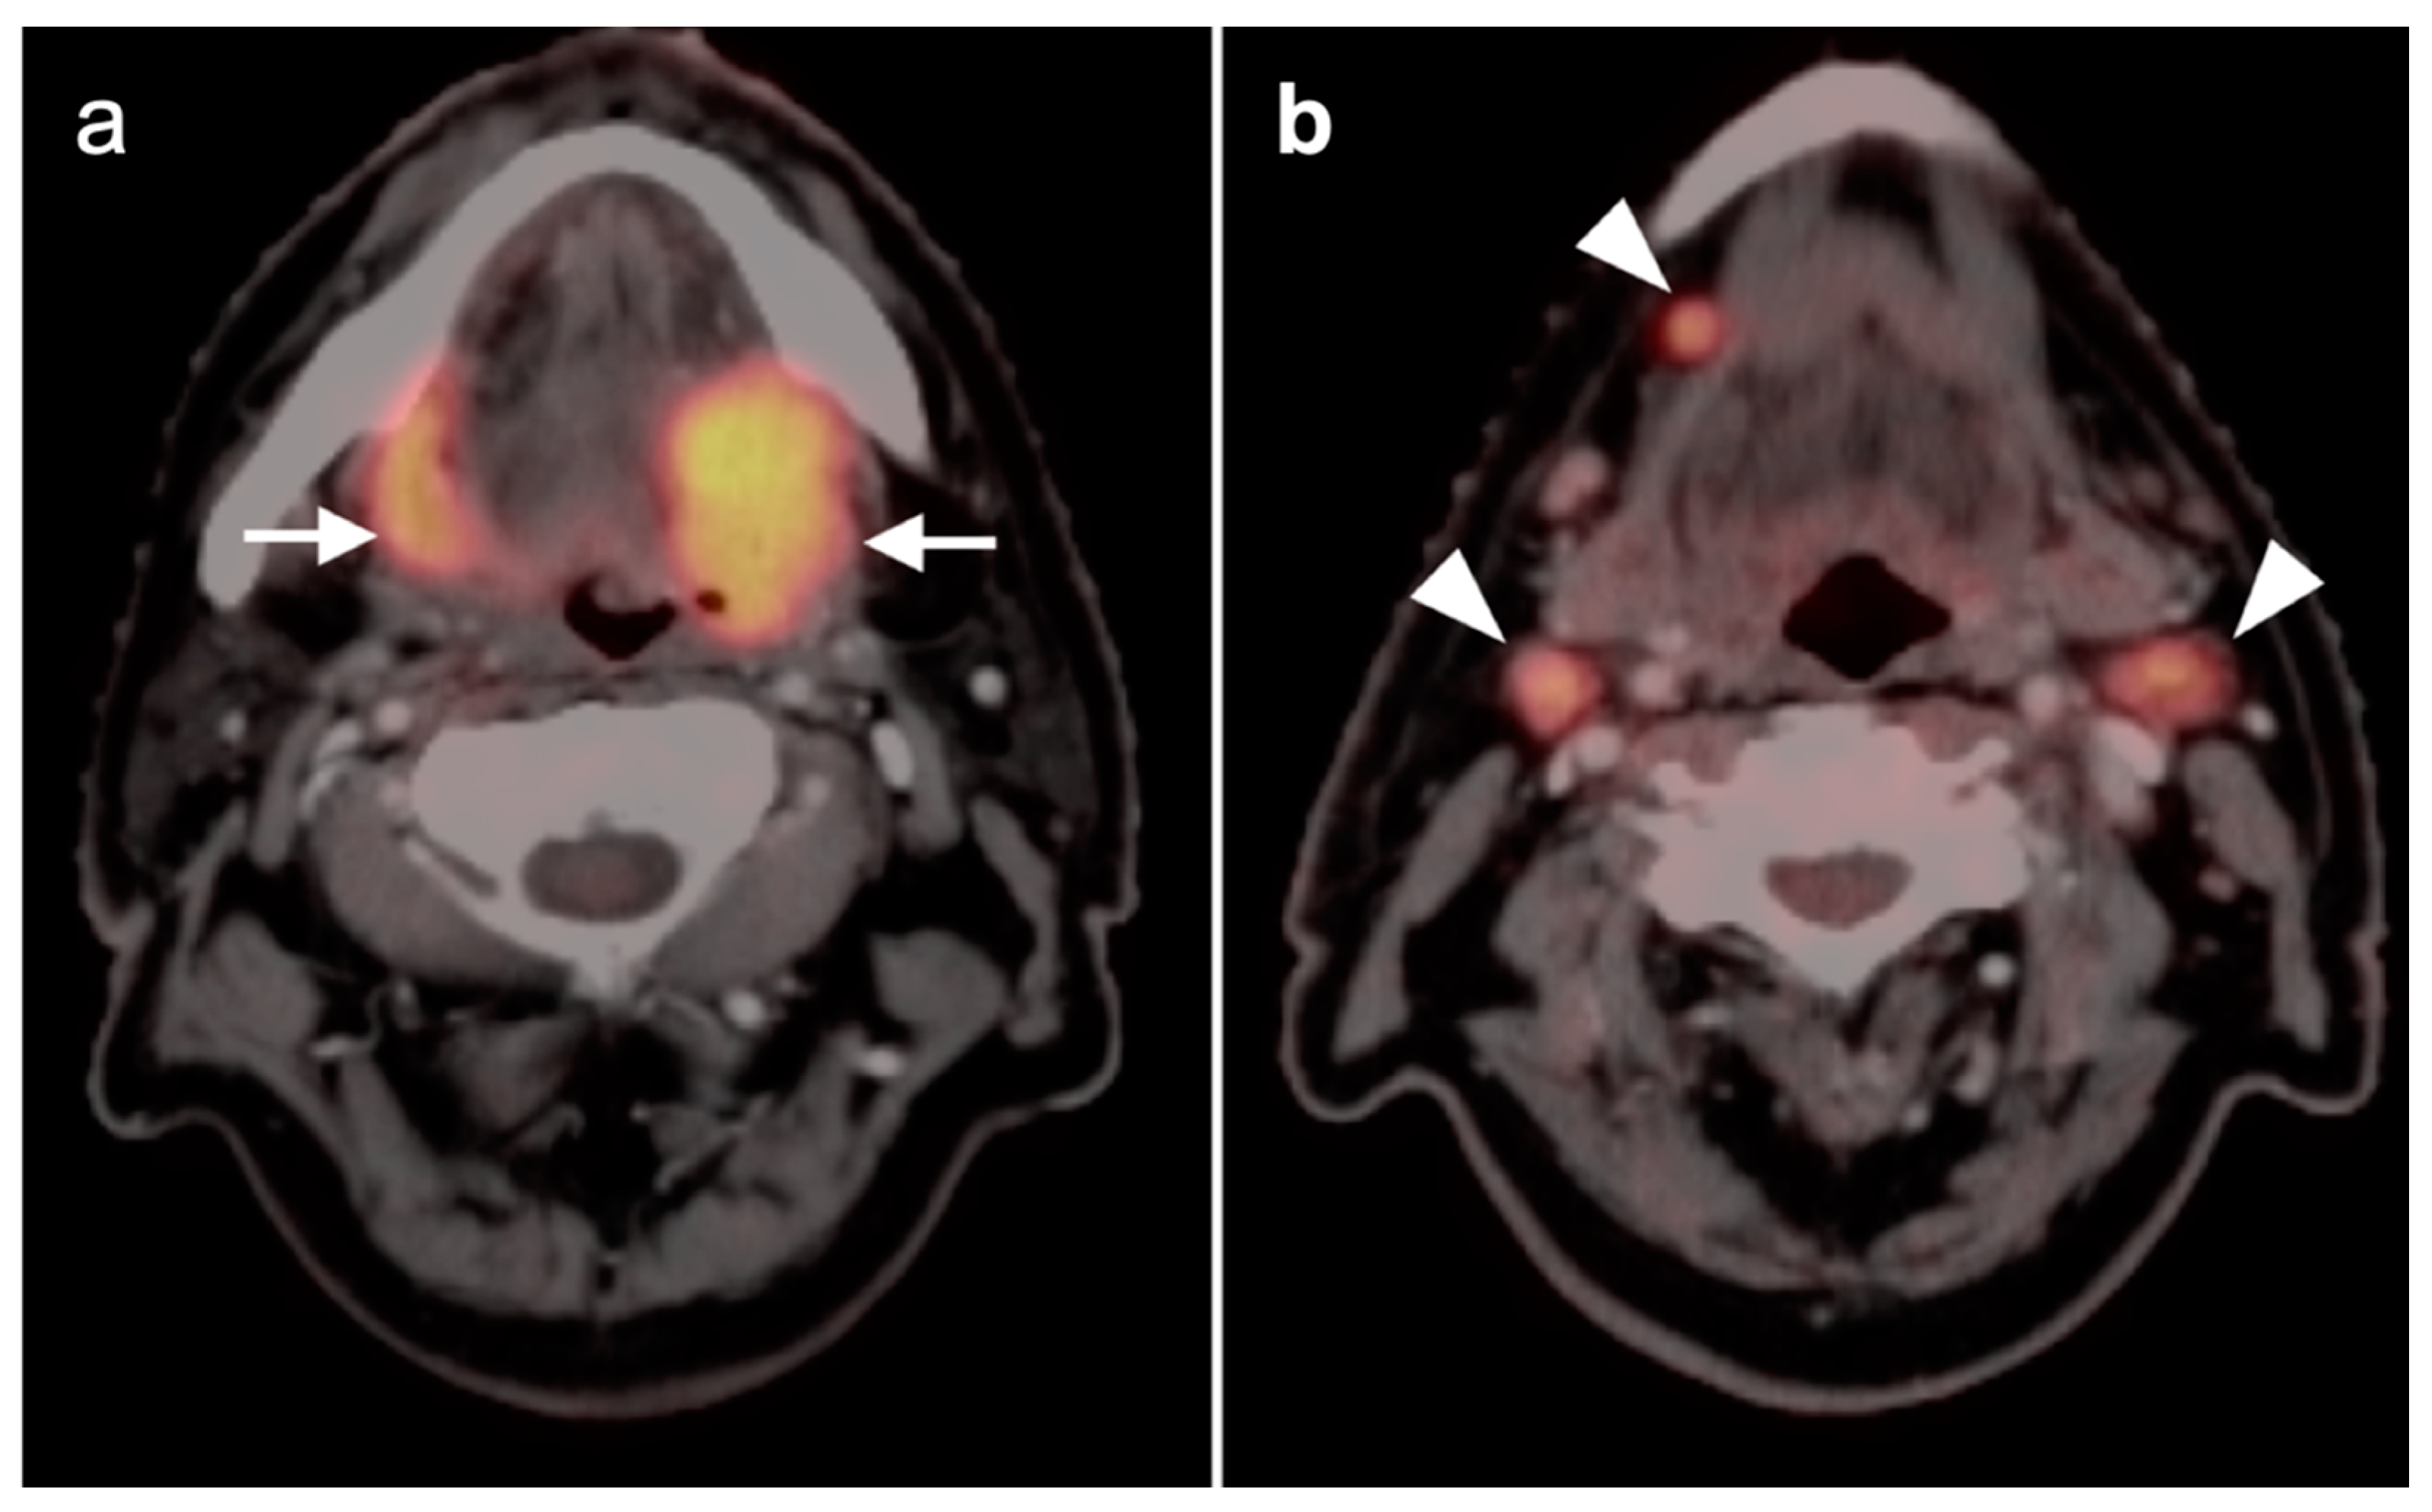

2.3. Nasopharyngeal Carcinoma